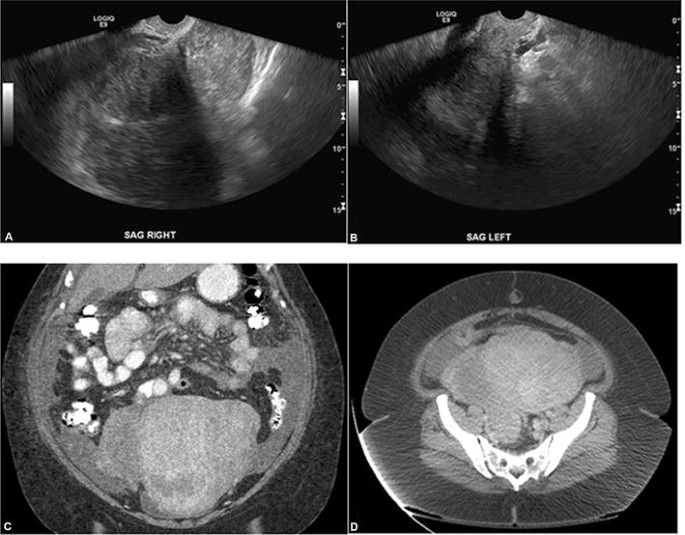

If the ovaries are not visualized, a doctor may order an ultrasound to get a better view of the ovaries. An ultrasound can help the doctor to identify any abnormalities in the ovaries, such as cysts or tumors. The ultrasound may also help to identify the cause of the non-visualization, such as endometriosis or adhesions.

If ovaries are not visualized during a pelvic ultrasound, it could be due to a number of different causes. It may be due to ovarian cysts or other masses in the ovaries that are blocking the view, or it could be due to the size and position of the ovary. It could also be due to a technical issue with the ultrasound machine.

In some cases, the ovaries may be too small to be seen, or they may be hidden behind other structures in the pelvis, such as the uterus or bowel. If this is the case, a different type of scan, such as an MRI or CT scan, may be required to view the ovaries.

If ovaries are not visualized during a pelvic ultrasound, it is important to understand the potential risks. Not being able to visualize the ovaries could lead to a delayed diagnosis of ovarian cancer, or other conditions such as endometriosis or ovarian cysts. It is important to discuss any potential risks with your doctor.

It is also important to understand that not being able to visualize the ovaries does not necessarily mean that there is a problem. In some cases, the ovaries may simply be too small or hidden by other structures. If this is the case, a different type of scan may be required to view the ovaries.